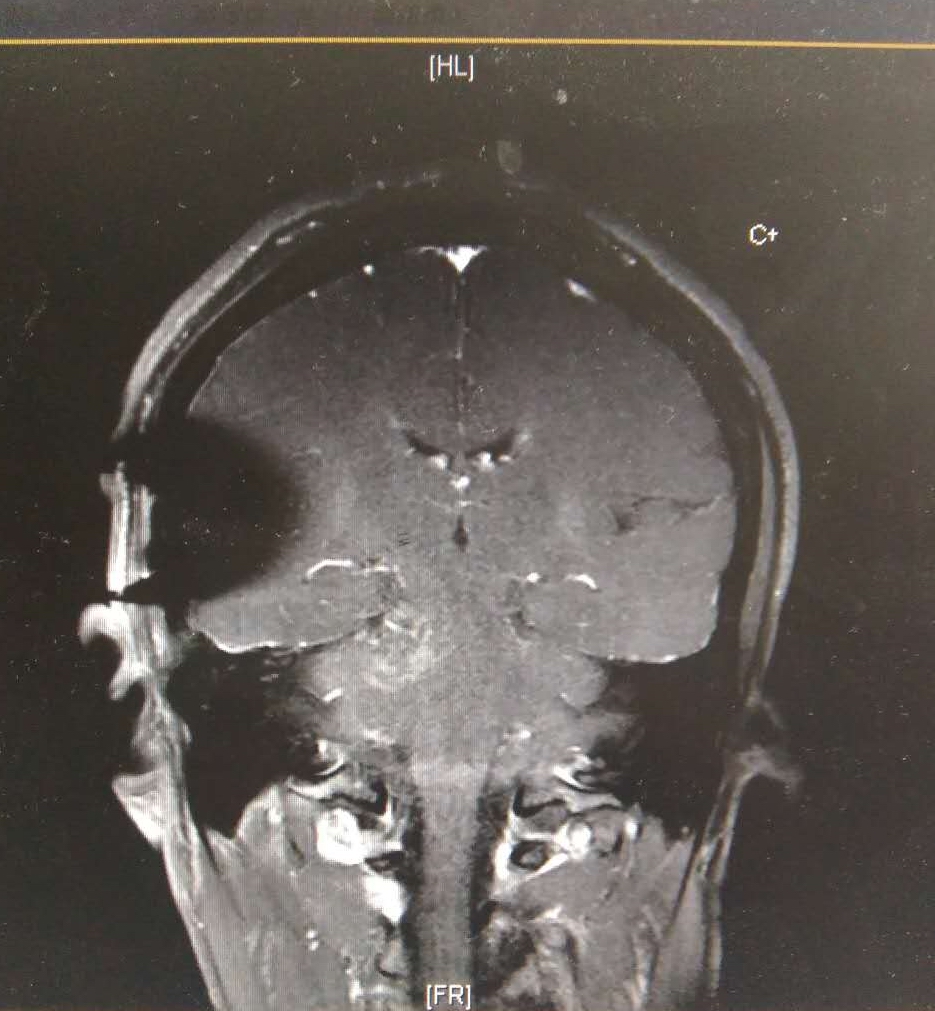

术后MRI,肿瘤全切